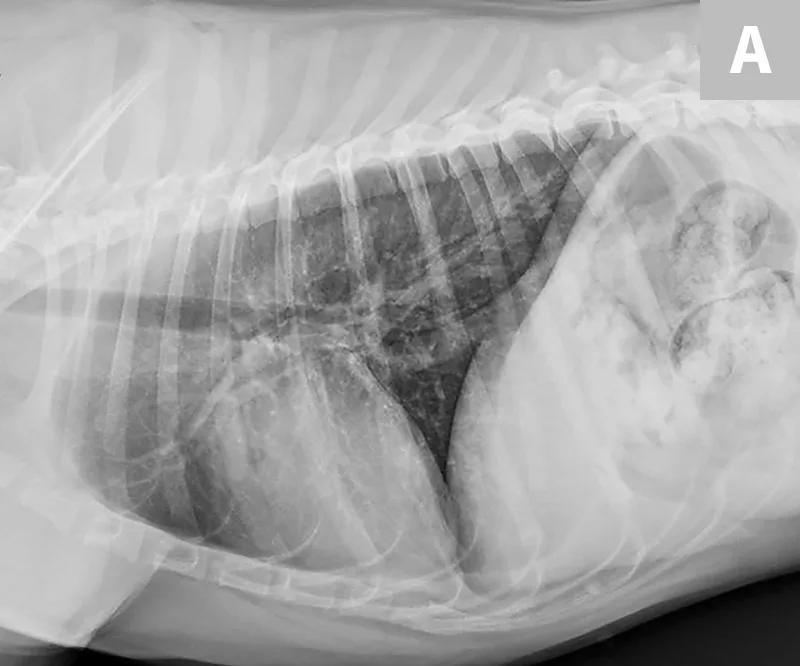

FIGURE 2

Single microfilaria in a blood smear